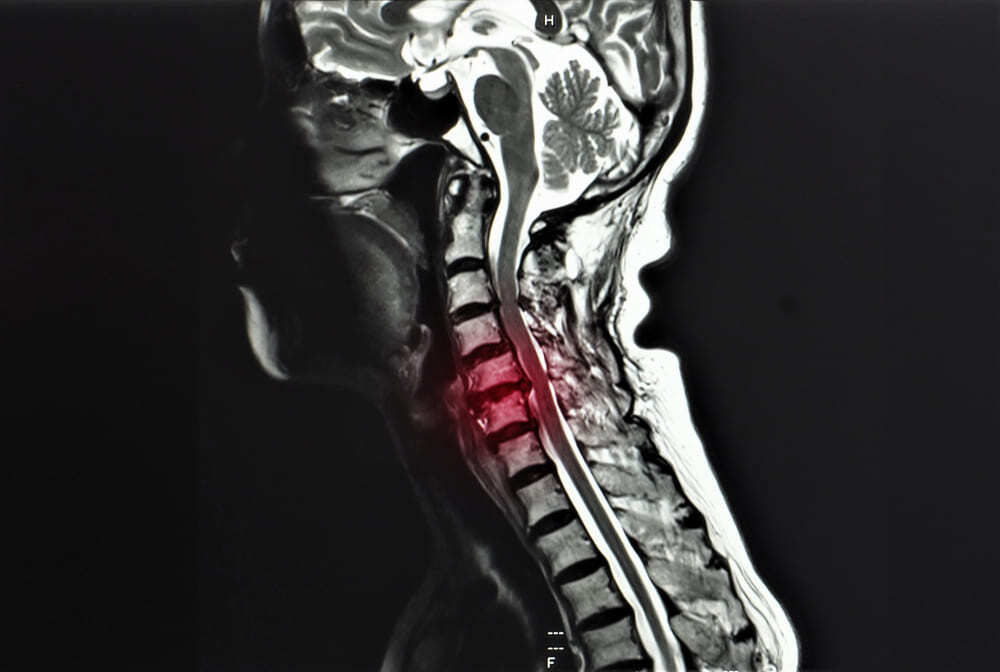

La mielopatía se desarrolla cuando la médula espinal sufre la compresión de las estructuras circundantes. Esta compresión puede deberse a una enfermedad degenerativa del disco, espolones óseos, hernias discales o estenosis espinal.

Esta enfermedad puede afectar a cualquier región de la columna vertebral. La mielopatía cervical se produce en el cuello y es la forma más frecuente, mientras que la mielopatía torácica afecta a la parte media de la espalda. Según un estudio del European Spine Journal, alrededor del 15% de los pacientes sufren un deterioro importante de la columna en tres años sin una intervención adecuada.